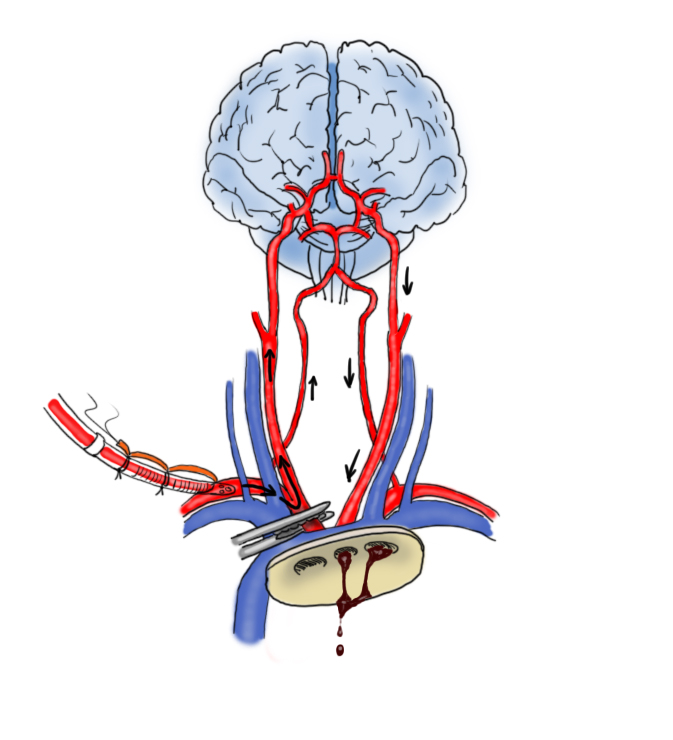

Storicamente, il primo tipo di perfusione cerebrale è stata la perfusione cerebrale retrograda (immagine sopra). In questa procedura, durante l’arresto cardiocircolatorio ipotermico viene inserita una cannula arteriosa nella vena cava superiore. Si imposta quindi un flusso tale da portare la pressione venosa intorno ai 20-25mmHg, sufficienti per invertire il flusso cerebrale (vena cava superiore → seni venosi → microcircolo → arterie). Questa tecnica è semplice ma ha una serie di difetti: non consente tempi di arresto prolungati, la distribuzione del flusso non è omogenea, la perfusione metabolica non è ottimale e vi è rischio di edema cerebrale. Nel corso degli anni è stata superata dalla perfusione cerebrale anterograda.